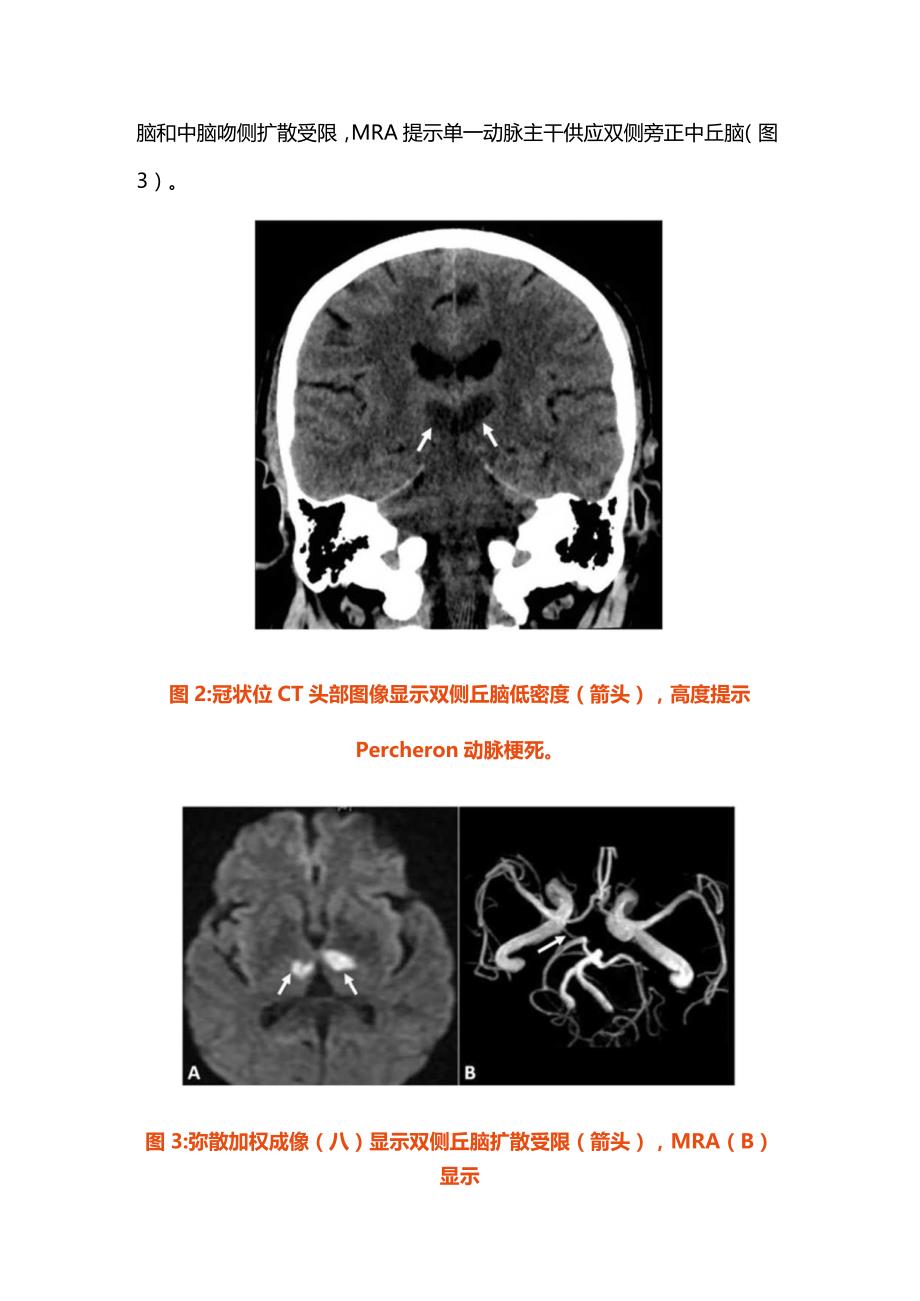

3、监护病房(ICU)进行进一步治疗管理。静脉给予降压药控制血压防止进一步脑损伤,在整个住院期间血压维持在120/80和140/9OmmHg之间。溶栓后72小时给予阿司匹林口服。住院期间还进行了完整的心脏检查,结果正常。基础实验室检查也未见明显异常。图1:头部CT轴位扫描显示左侧内曩后肢模糊的低密度影(箭头),提示急性缺血性脑卒中,与右侧肢体偏瘫的临床表现相符合。三天后复查头颅CT扫描显示双侧丘脑低密度影,与Percheron动脉区域的急性梗死一致(图2)。进一步查MRI证实了诊断,显示双侧丘脑和中脑吻侧扩散受限,MRA提示单一动脉主干供应双侧旁正中丘脑(图3)。图2:冠状位CT头部图像显示双侧丘

4、脑低密度(箭头),高度提示Percheron动脉梗死。图3:弥散加权成像(八)显示双侧丘脑扩散受限(箭头),MRA(B)显示单一动脉主干(箭头)供应丘脑,与Percheron梗死动脉一致。在接下来的几天里患者症状逐渐好转。格拉斯哥昏迷评分提高到14/15,国家卫生研究院卒中评分下降到8分。神经学查体显示症状有所改善,右侧肢体力量和构音障碍部分恢复。患者在住院期间出现轻度吞咽困难,通过调整饮食和语言治疗进行保守治疗。住院一周后,患者出院到康复机构接受进一步的恢复和康复。在康复过程中临床症状持续改善,最终遗留轻度肢体无力出院。出院时改良mRS评分为2分,提示轻度残疾,尽管无法进行发病前所有的活动,